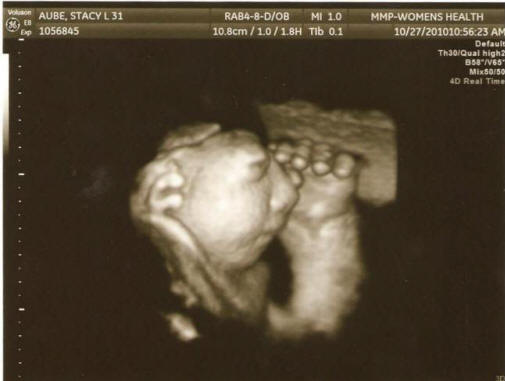

Fotografie z otevřených zdrojů zapojených do vyšetřování odborníci pored přes lékařské záznamy těhotných žen z 27 oblasti registrované na předporodních klinikách, kde studují pracovali, než byli nemocní, pili alkohol, drogy nebo uzené výrobky, v jaké oblasti žili a z čeho zdroj pil vodu. Koneckonců, vládní úředníci dospěl k závěru, že nebyli schopni zjistit „podmínky nebo důvody“ tohoto jevu. „Výsledky byly zklamáním, ale ne úplně neočekávaný, přijatý vědec Jim Kucik (Jim Kucik), který se zúčastnil ve studii. – Obvykle takové vrozené vady způsobují kombinace faktorů, které je velmi obtížné odhalit. Ne je možné, že to všechno je jen náhoda. “ A tady je genetika poradkyně Susie Ball věří, že ve třech krajích Ve státě Washington je nějaký problém, který by měl být dán větší pozornost s cílem chránit ženy v budoucnosti v plodném věku. Pozor, šokující fotka.

Fotografie z otevřených zdrojů “Nechtěl bych lidi vyděsit, ale.” to, co se děje, mě znepokojuje, “zdůraznila. – Přijato od informace zdravotnického personálu by měly být široce propagovány, aby ženy v plodném věku přijaly všechna nezbytná opatření zabránit rozvoji této patologie. Pro začátečníky jim radím vezměte kyselinu listovou. “ Vědci již výsledky přečetli předchozí studie identifikující potenciální faktory riziko rozvoje anencefalie: nízký obsah folátu v potravě kyseliny, vystavení pesticidům a znečištění pitné vody dusičnany.